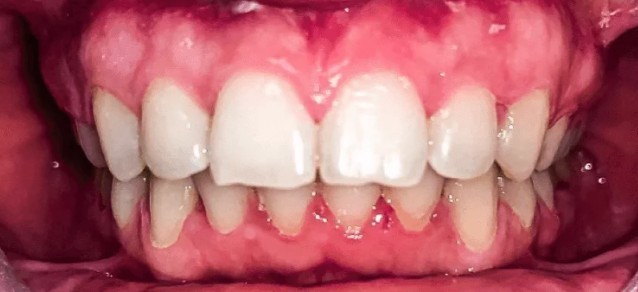

Установка сапфировых брекетов

Пациентка обратилась с жалобами на сильно выраженную скученность резцов нижнего зубного ряда. Также в ходе ортодонтического лечения 6-й зуб справа на верхней челюсти ортодонтическим способом «утопили» в костную ткань, поскольку зуб вышел из окклюзионной плоскости. Тем самым значительно уменьшилось оголение шейки зуба. Продолжительность лечения 1 год, сапфировые брекеты.

Доктор: Хачатрян Лариса Рубеновна